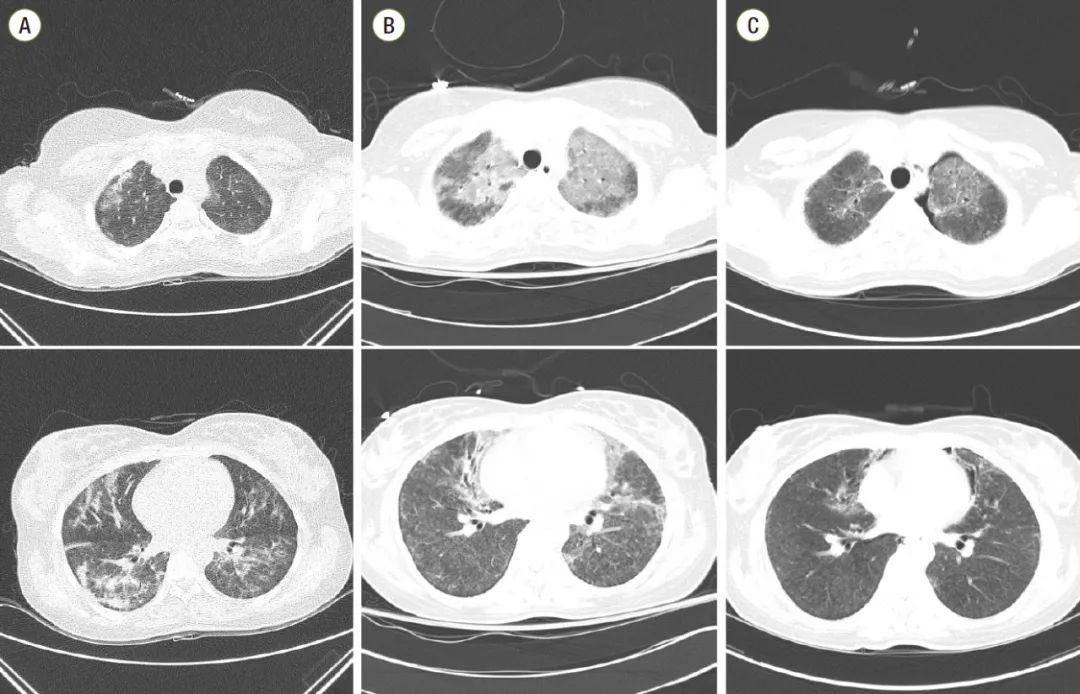

在事件发生后展开的调查也证实了这一点,经过动物实验,两组吸入不同杀菌剂的老鼠肺部在一个月后出现异常变化,和先前出现的肺病患者的肺部变化一致,证实了加湿器消毒剂的危害性。